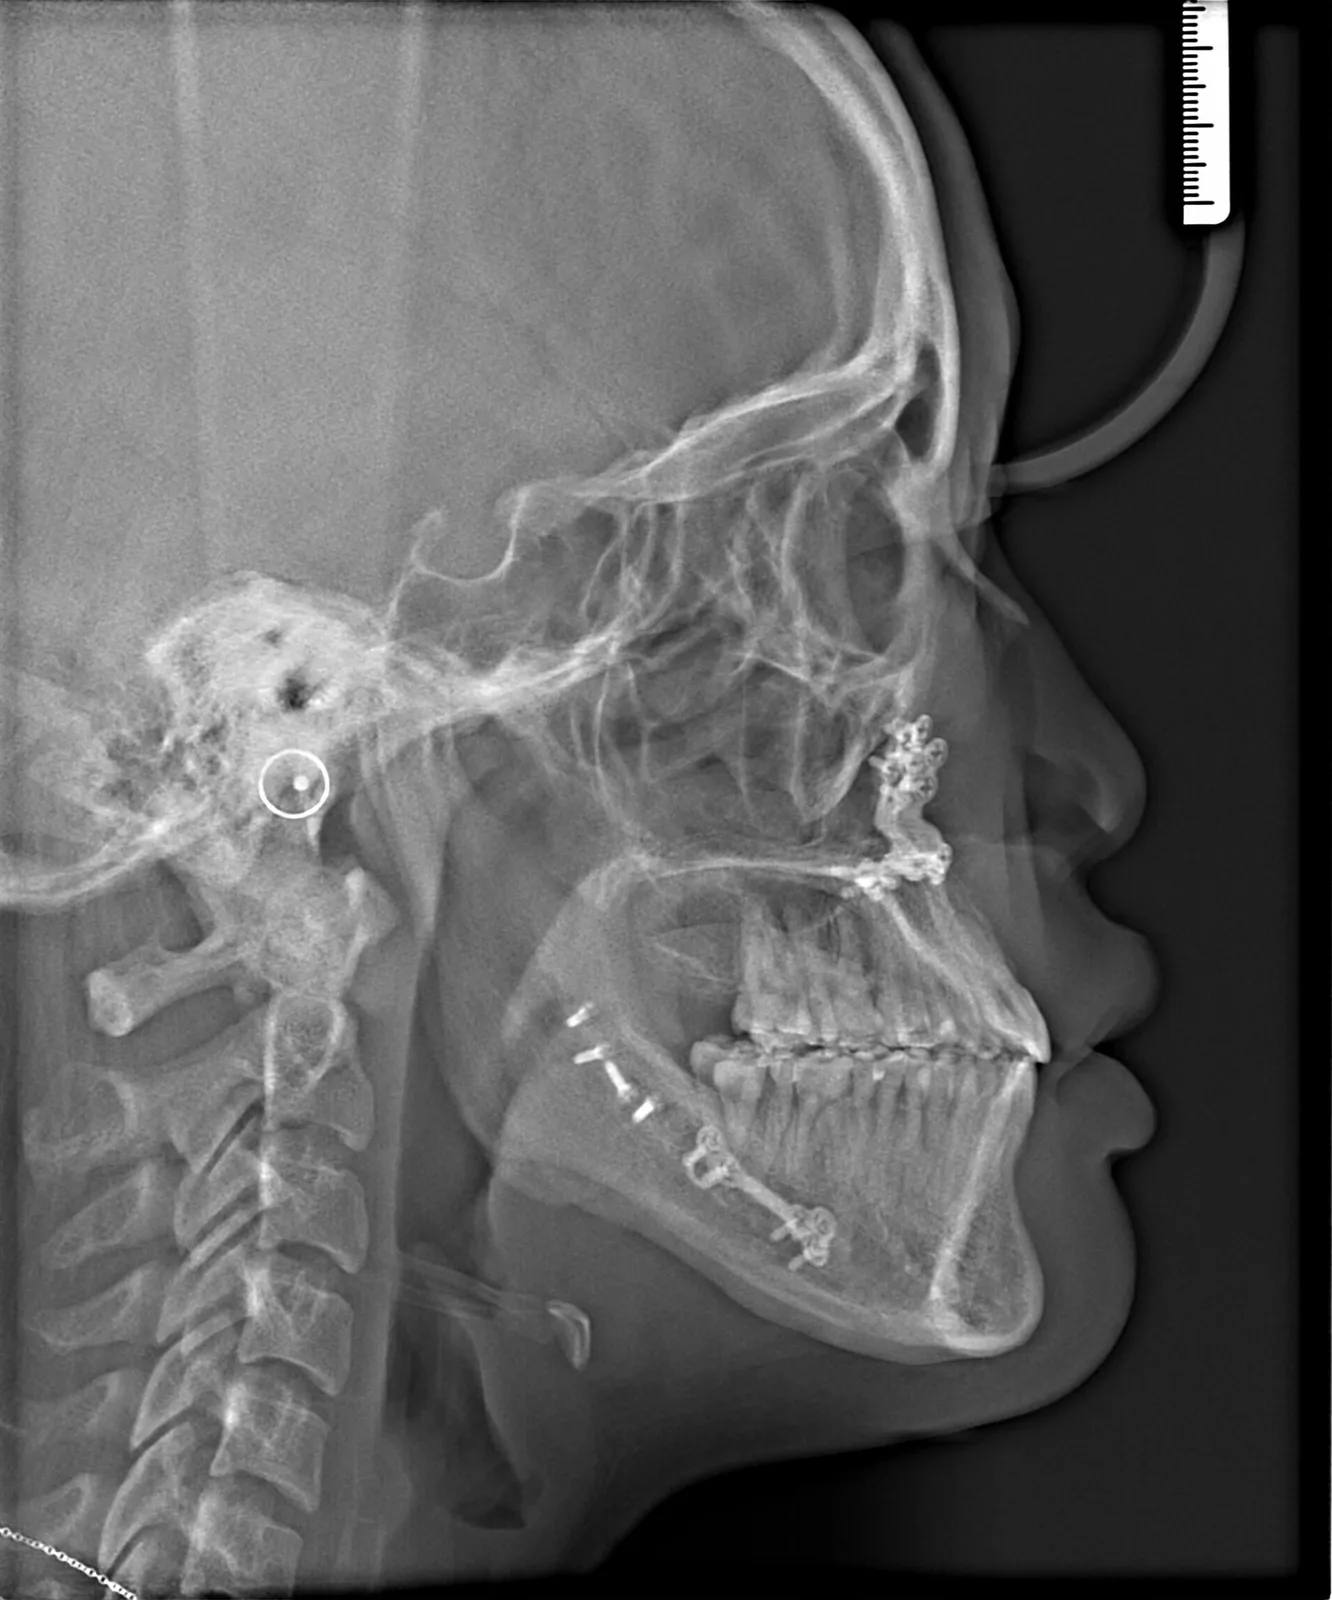

After Metal Self-Ligating Braces & Orthognathic Surgery: The Surgical Comeback smile results by Las Vegas Orthodontist Dr. Saoly Benson. Treatment approach: this transformation was designed with intention. After

After orthodontic x-ray: Cephalometric profile after Metal Self-Ligating Braces & Orthognathic Surgery showing skeletal correction by Dr. Saoly Benson. After

This transformation was designed with intention. Dr. Benson used braces to sculpt alignment and prepare the bite, then collaborated with an oral surgeon to reposition the mandible through orthognathic surgery. The result: a stable bite, restored facial balance, and symmetry achieved.